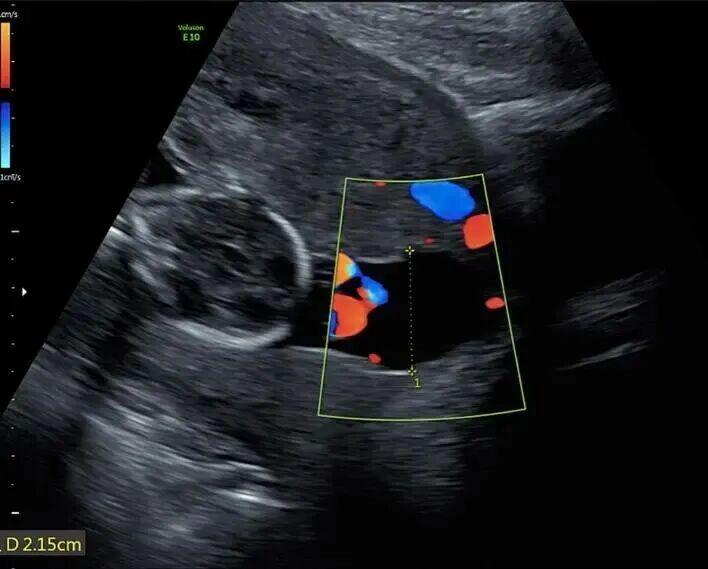

所以,她常规用药进行期待治疗,直至孕23周,大量羊水流失,超声显示宫内无羊水,也就是说羊水几乎已经流光。

医生在她子宫内放置了一根很细的专用导管,通过这根管子24小时不间断灌注一种特制的无菌营养液(每天2400毫升)。

目的是冲走细菌和炎症物质,为胎儿提供液体保护垫,防止肢体畸形和肺被压瘪,另外就是降低细菌浓度,为治疗争取时间。